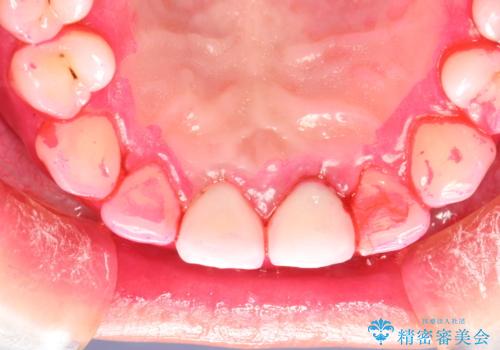

治療途中

-